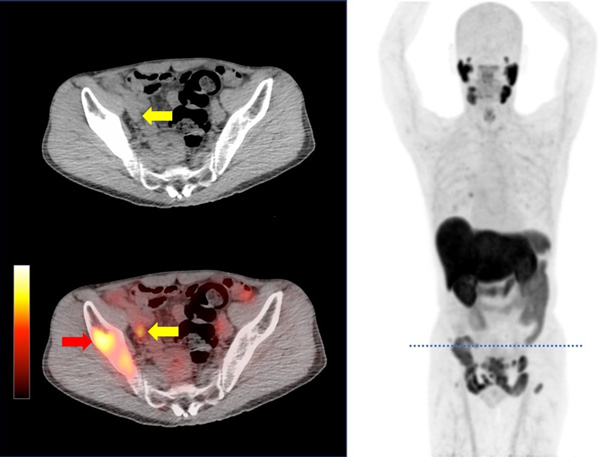

Imágen representativa de un PET-PSMA.